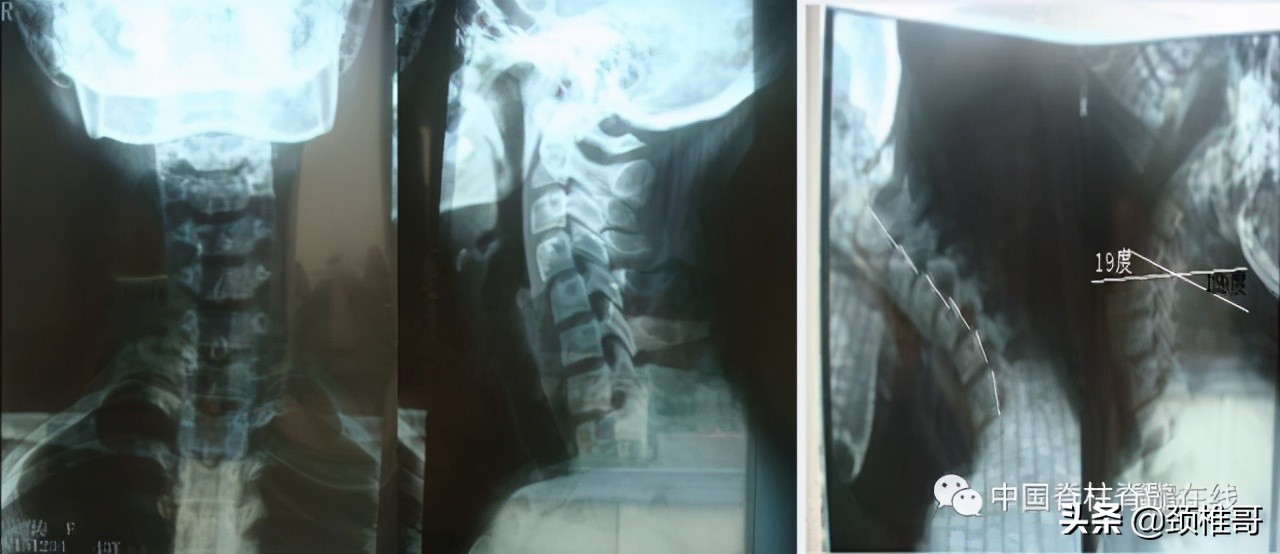

交感神经型颈椎病患者:颈椎MRI颈椎间盘正常、颈椎生理曲度异常

颈椎正侧位:序列 欠佳 动力位:颈椎3-6各个节段之间不稳